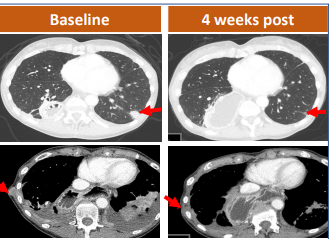

48岁的女性晚期胃腺癌患者,7.6cm的肿瘤已经通过造口蔓延到了腹外,CAR-T治疗4周后肿瘤显著缩小。

62岁的女性胃腺癌患者已经出现肺部转移,接受CAR-T治疗后仅4周,肺部的1个靶病灶完全消失,另外2个显著缩小。